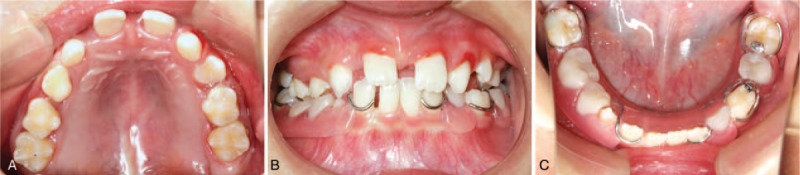

The extraoral examination presented no abnormity. Intraorally, the patient was in mixed dentition and the oral mucosa was normal. Examination revealed the presence of following teeth: #16, 55, 54, 53, 11, 21, 63, 64 65, 26, 36, 74, 31, 32, 41, 42, and 46 (Fig. 1). Tooth #24 and 43 were partially erupted. Her maxillary 2nd primary molars looked slightly abnormal in shape, with a comparatively larger cusp of Carabelli than usual. All other erupted teeth were regular in shape and color. All teeth were small in size with evident interdental spaces. The patient also had an anterior crossbite on her right maxillary canine. For exact diagnosis, we made a plaster cast and measured each erupted tooth 3 times including mesiodistal and labiolingual dimensions. The average value was obtained to improve measurement precision. All teeth were a smaller size than normal in every dimension (Tables 1 and 2). Moreover, the distal-occlusal caries of her mandible left 1st primary molar had periapical periodontitis, and the permanent successor had partially erupted. Furthermore, her mandible left 2nd primary molar had a deep caries lesion.

Figure 1.

Intraoral clinical photographs, including views of: (A) upper arch; (B) anterior; (C)lower arch.